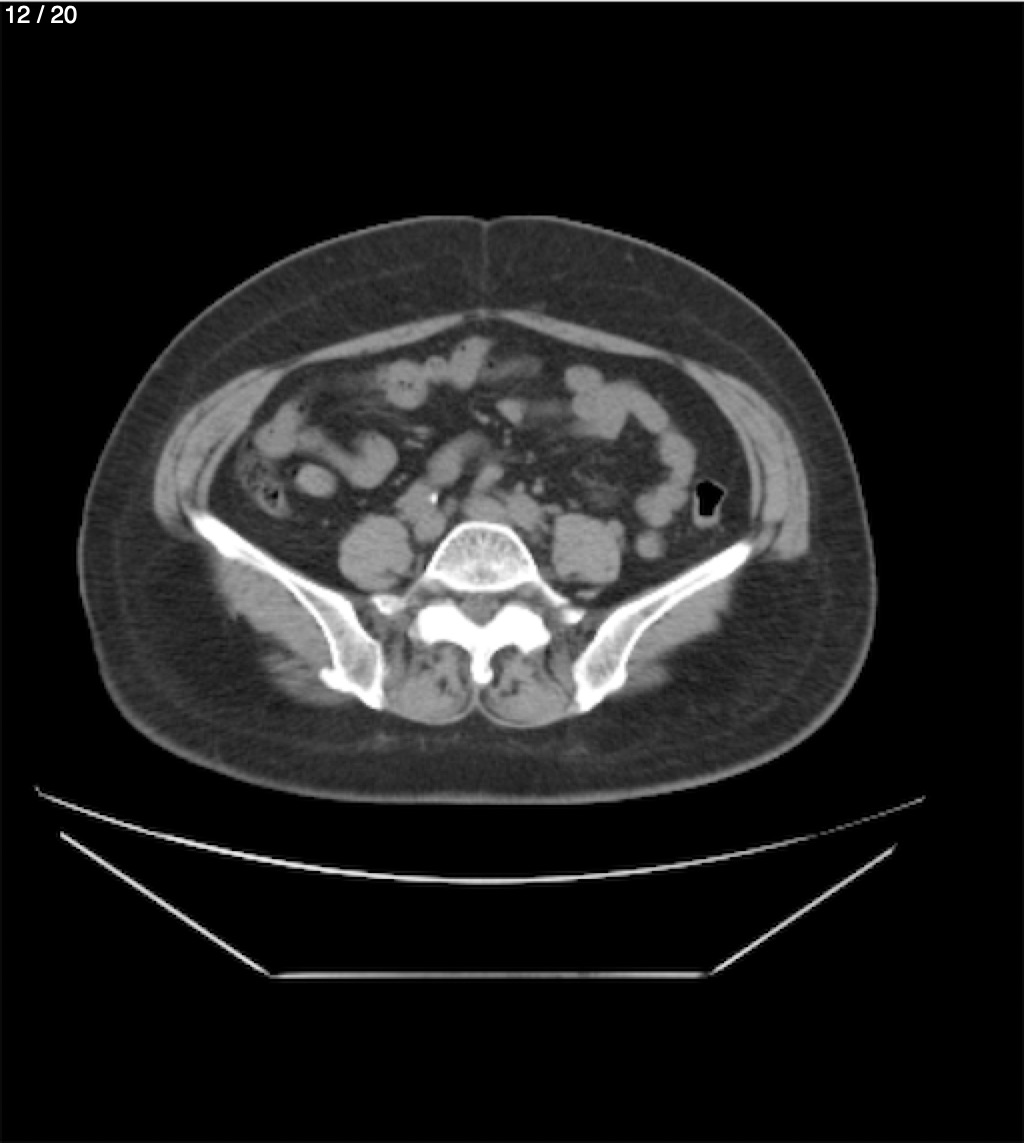

Maria Enrique Giron Dominguez63A - T.C Abdomen Simple